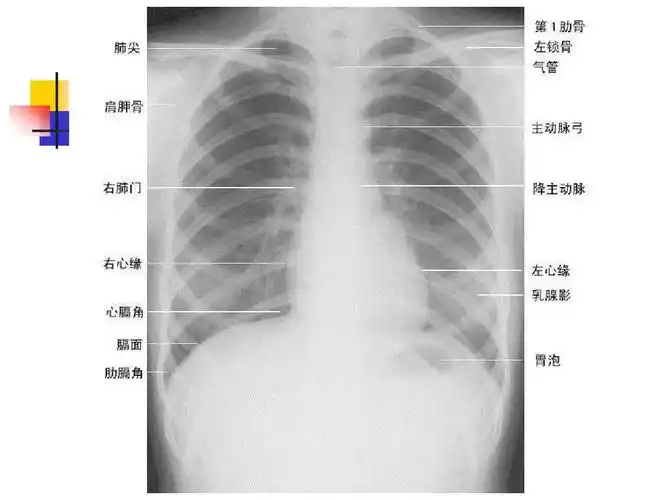

正常胸片胸部ct阅读

胸片影像